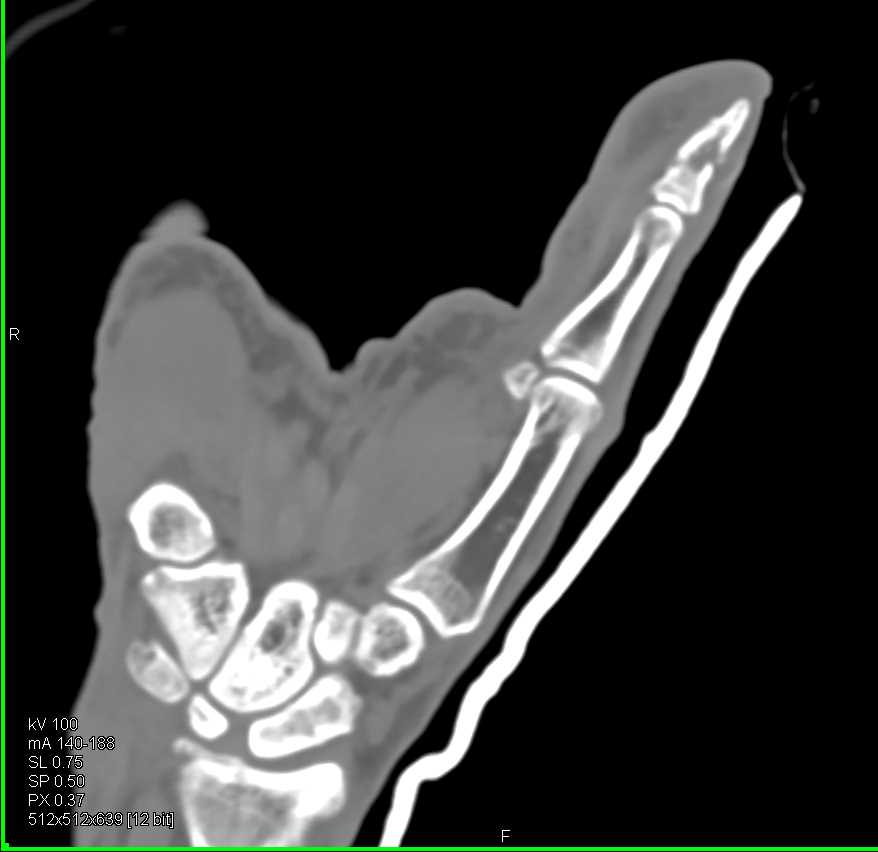

Diagnosis

Recurrent Renal Cell Carcinoma to Contralateral Kidney and Left Iliopsoas Muscle